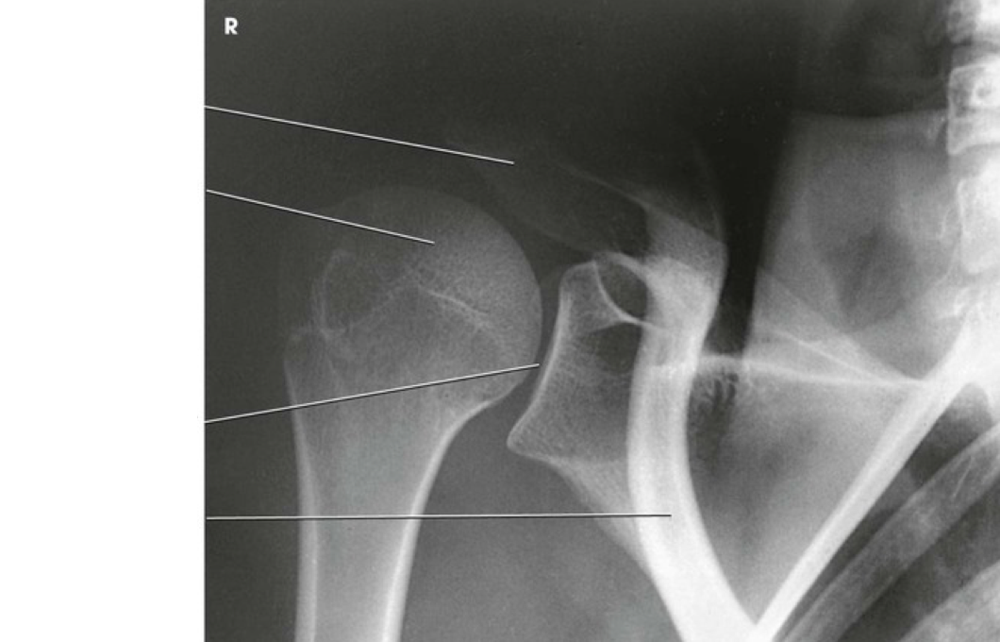

Question 1

Question

Label the image

Image:

3a528096-0507-46cb-a48d-05f40cfb6bb1 (image/png)

Answer

acromion

clavicle

coracoid process

glenoid cavity

lateral border of scapula

medial border of scapula

inferior angle of scapula